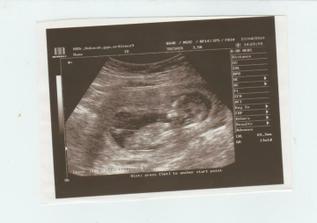

Konečně jsem svěřena do péče svého gynekologa a v 9tt první ultrazvuk u něj, za týden jsem dostala svou první těhotenskou knížku.